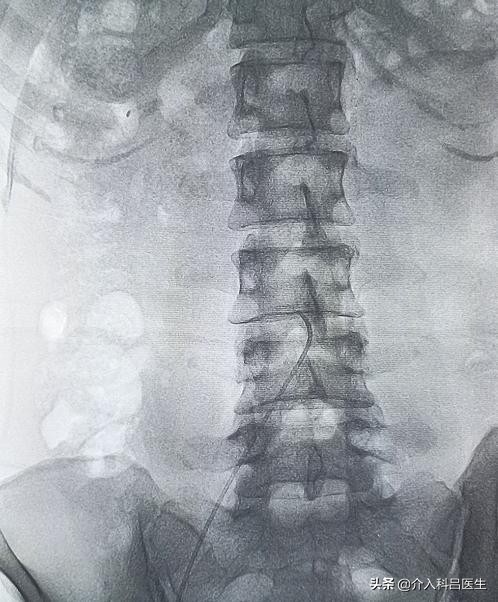

该治疗只需要在患者一侧的大腿根部用细针穿刺,仅有一个 2 毫米的针眼,并不需要进行全麻和开腹。将导管送到子宫肌瘤的供血动脉,推注尽可能小的颗粒型栓塞剂栓塞肌瘤,以阻断肌瘤的病理血管床,使其缺血坏死萎缩,达到“饿死”肌瘤的目的,既可使子宫肌瘤缩小或消失,又可保全子宫功能。介入治疗是在局部麻醉下完成的,手术时无痛苦。术后即可进食,6 小时~8 小时便可自由活动,3 天~5 天就可以出院,休息 7 天~10 天,能正常工作生活。